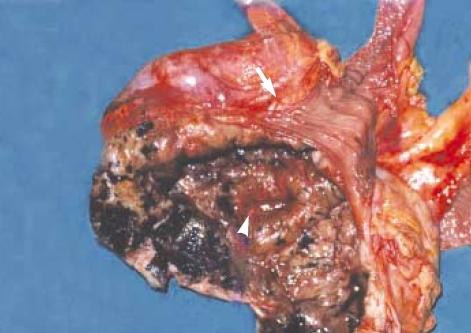

Malignant melanoma is the most common metastatic tumor of the gastrointestinal tract and can present with fairly common constitutional symptoms. A 36-yr-old woman was found to have a secondary malignant melanoma in the terminal ileum with profuse aneurysmal dilatation, which is not the typical presentation of the malignant melanoma in the small intestine. Radiologic studies revealed a large tumor involving the distal ileum with aneurysmal dilatations having afferent and efferent loops, which needed to be differentiated from malignant lymphoma and other gastrointestinal tumors. Exploratory laparotomy was done, and we found a huge mass with plentiful aneurysmal dilatations; much the same of the findings from the previous studies. Segmental resection with the surrounding omentum was done followed by end-to-end anastomosis between both ends of the remaining ileum. She had been free from any evidence of the local or systemic recurrence for one year after the completion of eighteen months of the subcutaneous interferon treatment; postoperatively however, the occurrence of metastatic mass at the right axilla rendered us from complete resection due to severe penetration into the vital nerves and vessels in the axilla.

恶性黑色素瘤是胃肠道最常见的转移性肿瘤,可表现出相当常见的全身症状。一名36岁女性被发现回肠末端有继发性恶性黑色素瘤,伴有大量动脉瘤样扩张,这并非小肠恶性黑色素瘤的典型表现。影像学研究显示,一个大肿瘤累及回肠远端,伴有动脉瘤样扩张,有输入袢和输出袢,需要与恶性淋巴瘤和其他胃肠道肿瘤相鉴别。进行了剖腹探查术,我们发现一个巨大肿块,有大量动脉瘤样扩张;与先前研究的发现大致相同。进行了包括周围网膜的节段性切除,然后对剩余回肠两端进行端端吻合。在完成18个月的皮下干扰素治疗后,她有一年没有任何局部或全身复发的迹象;然而,术后右腋窝出现转移性肿块,由于严重侵犯腋窝重要神经和血管,我们无法进行完全切除。